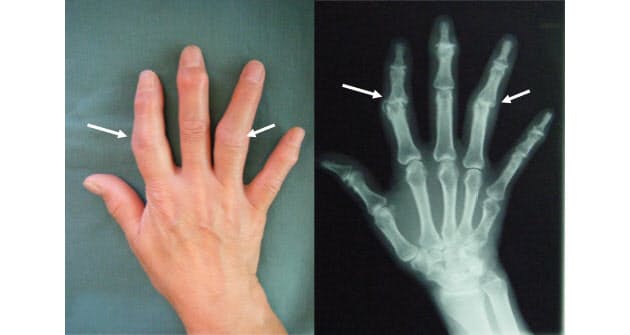

ヘバーデン結節 ブシャール結節 古東整形外科 リウマチ科

指が太くなる原因は何? 細くてスラっとした指は綺麗で憧れますよね。 でも、指が太くなってしまう原因は生まれつき骨格などで決まっているから細くすることはできないって思いますよね。 確かに指の骨格の違いなどで太かったり細かっ 指関節の骨を覆う軟骨がすり減って、指に痛みや変形が現れます。 同士がぶるかり、関節の周囲に「骨棘(こっきょく)」と言うトゲのようなものができ、関節が太く見えるようになってきます。 原因 ヘバーデン結節・ブシャール結節が起こる原因 指関節の黒ずみを確実に美白したいなら、黒ずみの原因を知り、正しい方法でケアすることがとても大切。 間違ったケアをつづけていると、アナタの指の関節はますます黒 ずんでしまうかもしれません 。 そこで、この記事では、指関節の黒ずみにお悩みのアナタに、"指関節"が黒ずむ原因